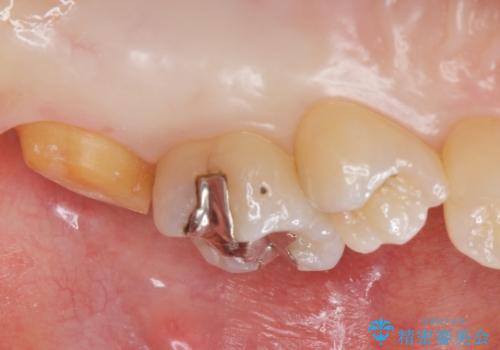

- 奥歯の歯が黒いとの事で来院された患者様です。

頬側の歯の面も粗造になっていたので、インレーではなくジルコニアクラウンでの治療となりました。